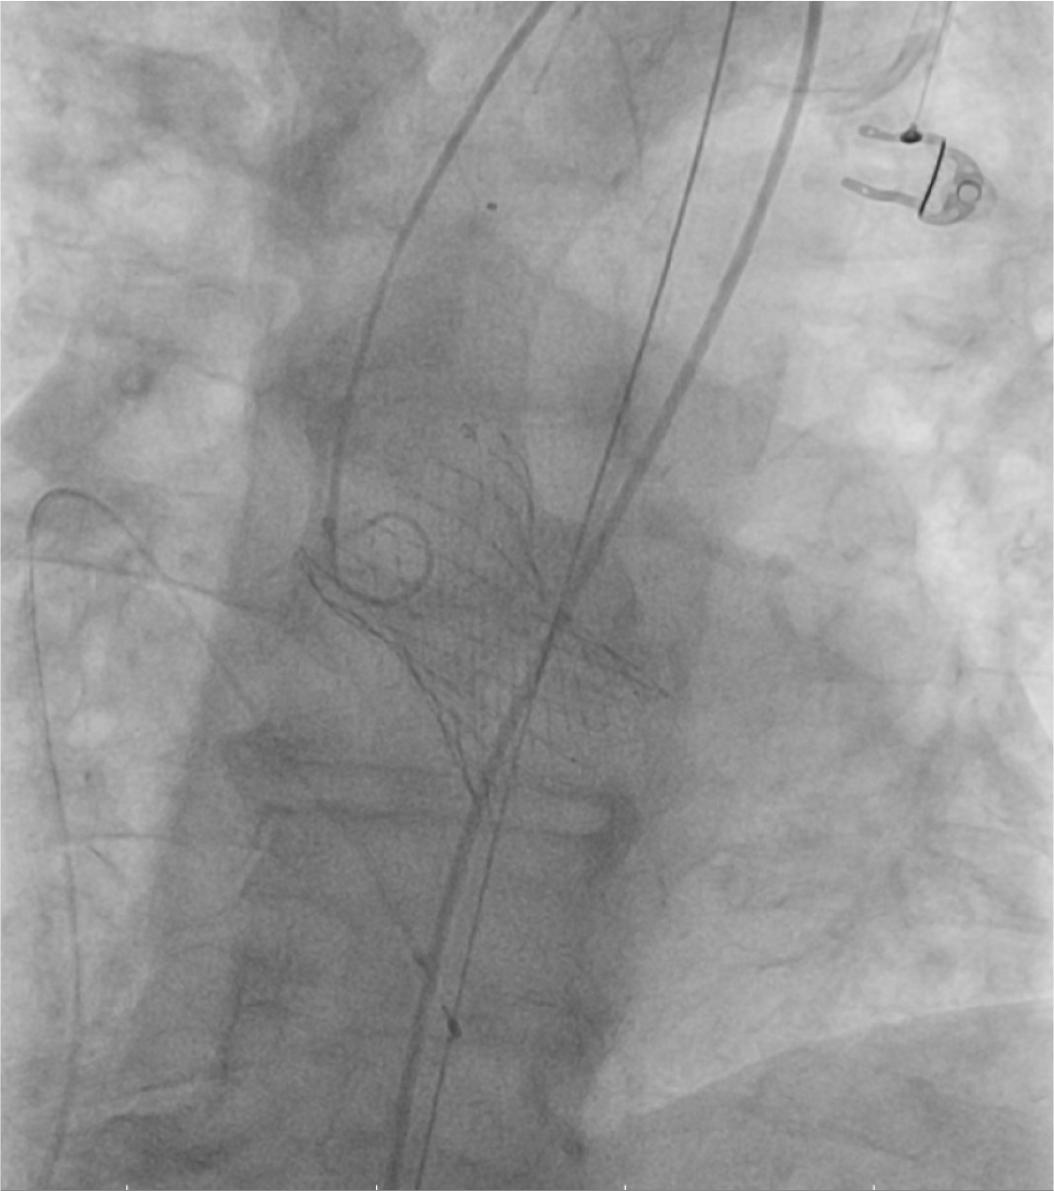

According to the European guidelines, aortic valve replacement should be considered before the the aortic aneurysmal repair. The patient was considered to be an intermediate risk candidate for surgical aortic valve replacement according to the EuroSCORE II (7%) and STS (8.2%) scoring systems, but given the association of patient’s frailty, advanced age (> 75 years), restricted mobility due to osteoporotic joint disease and the presence of a large abdominal aortic aneurysm, the Heart Team decided that the optimal treatment strategy for this patient is the transcatheter approach, TAVR followed by EVAR. The procedure was performed under spontaneous ventilation, with conscious sedation. A temporary pacing wire was inserted in the right ventricle, through the left common femoral vein to provide backup pacing in case of atrioventricular block development and rapid pacing for correct valve positioning. Bilateral percutaneous femoral access was obtained using the Seldinger technique, followed by pre-closure on both sides with two Proglide 6 Fr devices placed in a standard way. A 29 mm Medtronic Evolut R valve was inserted by an 18-French Sentrant Metronic sheath through the right femoral artery. After the direct deployment of the valve and balloon post-dilation under rapid pacing, the valve was correctly positioned and expanded (Figure 1), with a minor aortic insufficiency due to a paravalvular leak.

Fluoroscopic image: deployment of the Medtronic valve.